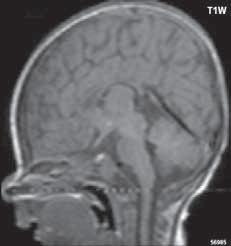

Obr. I.1.7a Sestup mozečkových tonzil (šipka), Chiariho malformace I

Obr. I.1.7b Sestup mozečkových tonzil, „pek like“ (šipka), Chiariho malformace I c d

Zobrazení

Chiari I: CT a MR zobrazí malou zadní jámu lební, absenci cisteren zadní jámy lební, pokles tonzil, krátký a konkávní klivus, poruchu cirkulace mozkomíšního moku v oblasti foramen magnum a následný hydrocefalus. MR navíc může prokázat edém krční míchy a ve vysokém procentu případů hydrosyringomyelii.